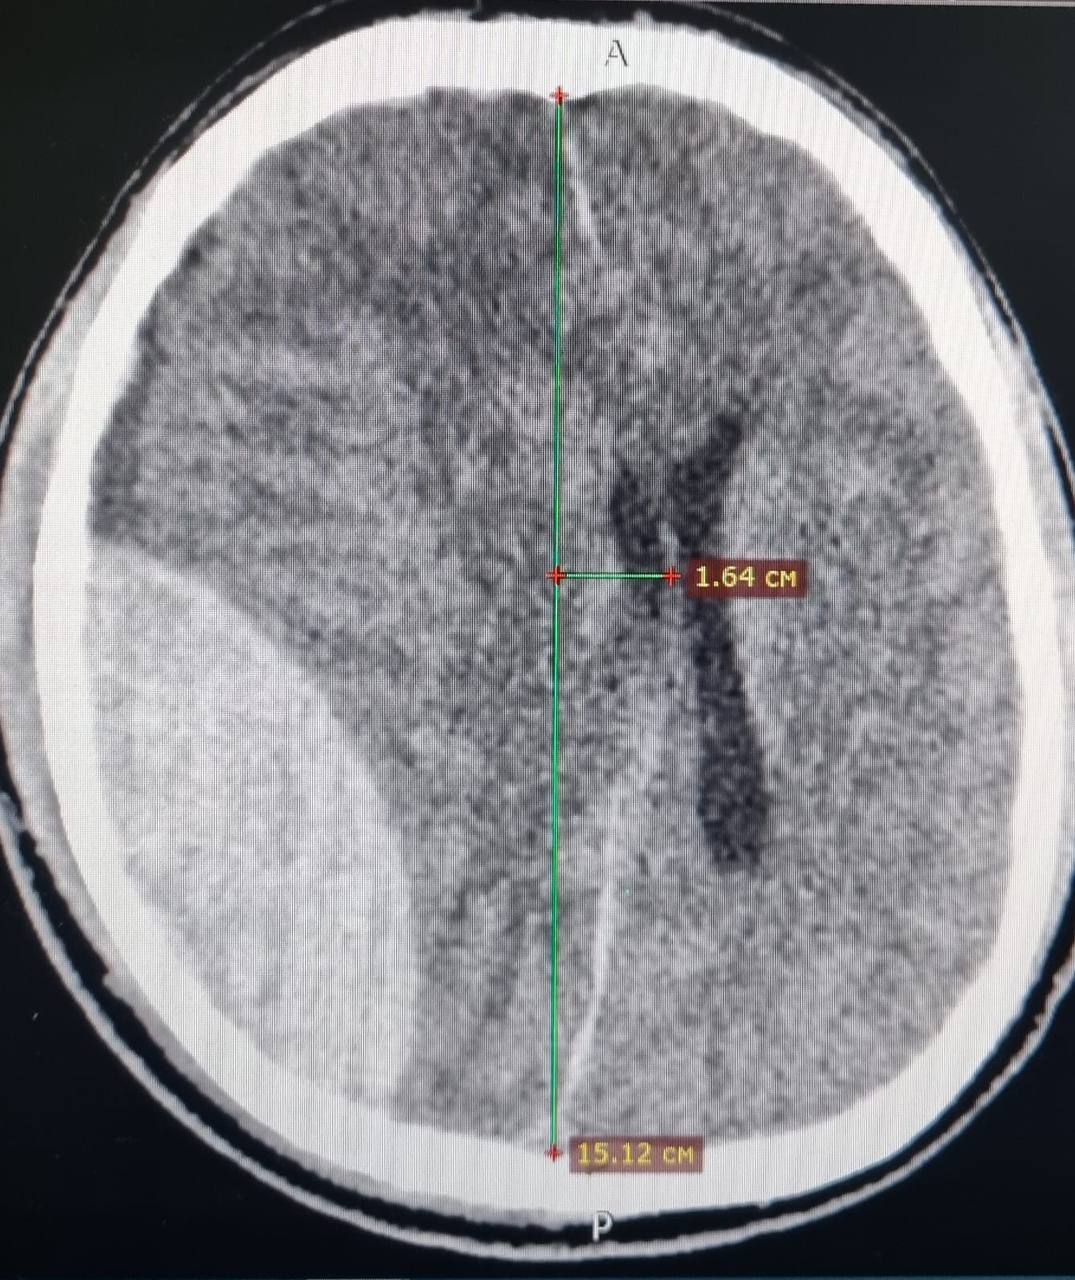

В больнице выяснилось: у пациента перелом черепа и массивная эпидуральная гематома (около 70 мл крови), сдавливающая мозг и вызвавшая отек и смещение его структур. Это крайне опасное состояние: такие гематомы встречаются реже чем у 2% всех черепно-мозговых травм, поэтому каждая минута промедления может стоить жизни. После операции ессентучанин оставался в глубокой коме и не было никаких гарантий, что он выживет. Но на десятый день мужчина все-таки пришел в сознание и даже начал дышать сам. Сегодня он чувствует себя отлично и уже готовится к выписке после второй операции.